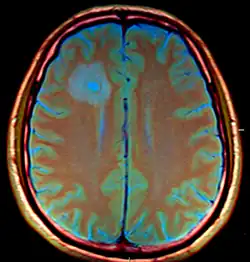

| Brain abscess in a person with a CSF shunt. The abscess is the darker gray region in the lower left of the image (corresponding to the right parietal lobe). The lateral ventricles are visible in black in the center of the brain, adjacent to the abscess.[1] | |

Brain abscess (or cerebral abscess) is an abscess within the brain tissue caused by inflammation and collection of infected material coming from local (ear infection, dental abscess, infection of paranasal sinuses, infection of the mastoid air cells of the temporal bone, epidural abscess) or remote (lung, heart, kidney etc.) infectious sources. The infection may also be introduced through a skull fracture following a head trauma or surgical procedures. Brain abscess is usually associated with congenital heart disease in young children. It may occur at any age but is most frequent in the third decade of life.